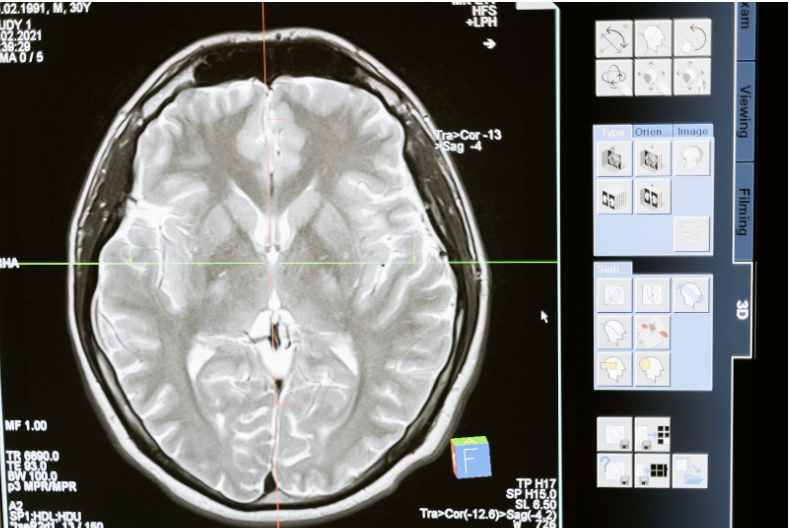

Le diagnostic de l’encéphalite se base sur une combinaison d’examens d’imagerie médicale (IRM) et d’analyse de liquide céphalorachidien (LCR) prélevé à l’aide d’une ponction lombaire. Ces tests aident le corps médical à identifier la cause sous-jacente de l’inflammation mais aussi à évaluer la gravité de la pathologie. En cas d’encéphalite infectieuse, les virus se retrouveront dans le liquide céphalo-rachidien. Lorsqu’elle est auto-immune, l’analyse de liquide céphalo-rachidien est dite négative. Cependant, certains virus ne se retrouvent pas dans le LCR.